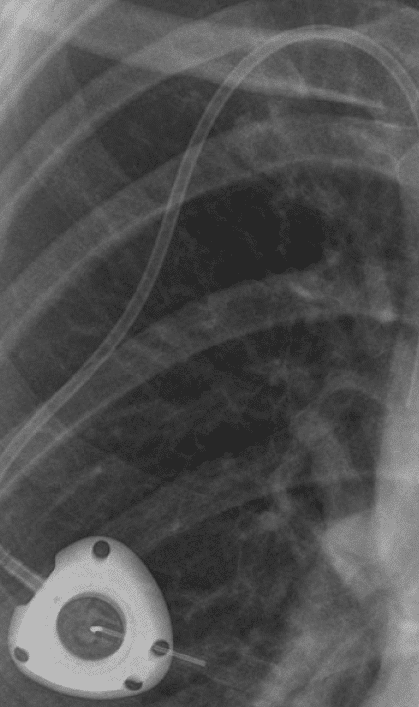

Bard Powerport is a brand name for a medical device designed for surgical implantation in the human body. It provides health care providers with direct access to a vein to deliver medications, intravenous fluids, nutrition, or blood products. It is a convenient method of avoiding frequent patient contact with needles. They are commonly used for chemotherapy in cancer patients.

The catheter is made from a type of polyurethane and silicone. It contains barium sulfate, a contrast dye that makes the port more visible during imaging tests, such as X-rays and CT scans. Unfortunately, barium sulfate has been shown to degrade polyurethane and silicone when in contact with human tissue.